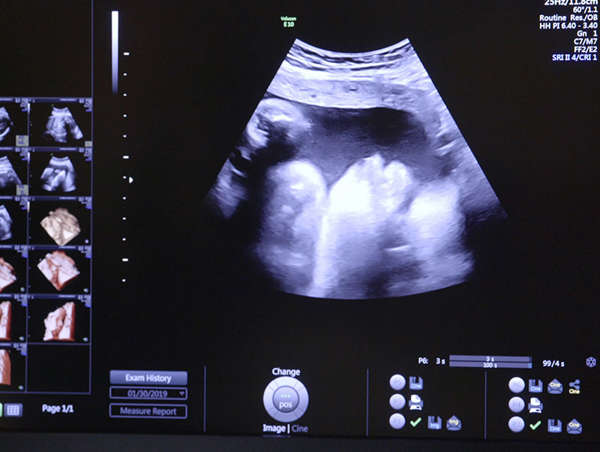

Jennifer was expecting her second child when she joined ReNew in 2019, four months before her son, Levi, was born. “I struggled with addiction off and on for almost 10 years,” she said, referring to her opioid dependency, which began with a medical prescription. Eventually Jennifer felt she couldn’t function properly without the opiates, and that became a problem when her doctor would no longer prescribe them to her.